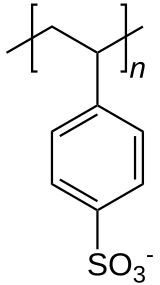

| Formula | [C8H7SO3−] n |

Common side effects include loss of appetite, gastrointestinal upset, constipation, and low blood calcium.[1] These polymers are derived from polystyrene by the addition of sulfonate functional groups.

Production and chemical structure

Polystyrene sulfonic acid, the acid whose salts are the polystyrene sulfonates, has the idealized formula (CH2CHC6H4SO3H)n. The material is prepared by sulfonation of polystyrene:

- (CH2CHC6H5)n + n SO3 → (CH2CHC6H4SO3H)n

Several methods exist for this conversion, which can lead to varying degree of sulfonation. Usually the polystyrene is crosslinked, which keeps the polymer from dissolving. Since the sulfonic acid group (SO3H) is strongly acidic, this polymer neutralizes bases. In this way, various salts of the polymer can be prepared, leading to sodium, calcium, and other salts:

- (CH2CHC6H4SO3H)n + n NaOH → (CH2CHC6H4SO3Na)n + n H2O

These ion-containing polymers are called ionomers.

Alternative sulfonation methods

Double substitutions of the phenyl rings are known to occur, even with conversions well below 100%. Crosslinking reactions are also found, where condensation of two sulfonic acid groups yields a sulfonyl crosslink. On the other hand, the use of milder conditions such as acetyl sulfate leads to incomplete sulfonation. Recently, the atom transfer radical polymerization (ATRP) of protected styrene sulfonates has been reported,[12][13] leading to well defined linear polymers, as well as more complicated molecular architectures.[14]